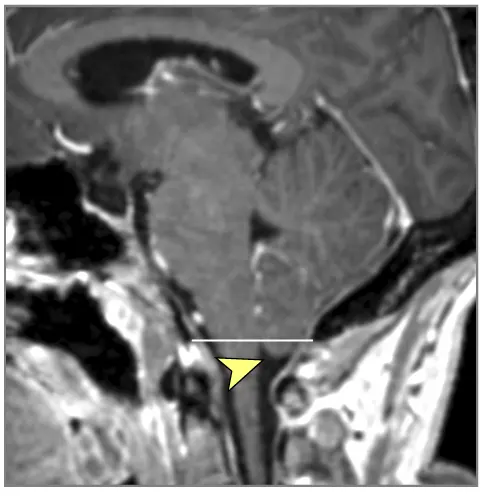

მრტ მიგნებები, რომლებიც მიუთითებს ინტრაკრანიალურ ჰიპერტენზიაზე (ხშირად ჩანს IIH-ში, მაგრამ შეიძლება მოხდეს ქრონიკული აწეული ICP-ის სხვა მიზეზებით) [9]:

- თავის ტვინის მრტ: სასურველი მოდალობა დეტალური ანატომიური შეფასებისთვის. შეუძლია აჩვენოს პარკუჭების გადიდება (ჰიდროცეფალია), გამოავლინოს ობსტრუქციული დაზიანებები (სიმსივნეები, კისტები, წყალსადენის სტენოზი), აჩვენოს მომატებული ICP-ის გართულებები (თიაქარი), აღმოაჩინოს კომუნიკაციური ჰიდროცეფალიის მიზეზები (მაგ., წინა სისხლჩაქცევის/ინფექციის ნიშნები), გამოავლინოს IIH-ის მიმანიშნებელი ნიშნები (ცარიელი კეხი, მხედველობის ნერვის გარსის გაფართოება, უკანა თვალის კაკლის გაბრტყელება, ვენური სინუსის სტენოზი MRV-ზე), ან აჩვენოს ცერებრალური შეშუპების გამომწვევი ძირითადი პათოლოგია (ინსულტი, სიმსივნე, ანთება) (7). სპეციფიკურ მიმდევრობებს (მაგ., CISS/FIESTA) შეუძლიათ შეაფასონ ლიკვორის ნაკადის დინამიკა.